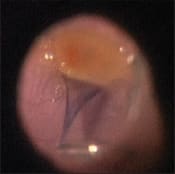

The ILM can be stained with Membrane Blue, although the quality of staining is variable, sometimes very faint and at other times quite prominent (Figure 3). With concerns about indocynanine green toxicity, Membrane Blue may be a safer option in macular hole cases. Later in this article, I will discuss several techniques to increase the quality of ILM staining.

Figure 3. Partially peeled internal limiting membrane stained with Membrane Blue in a case of macular hole.